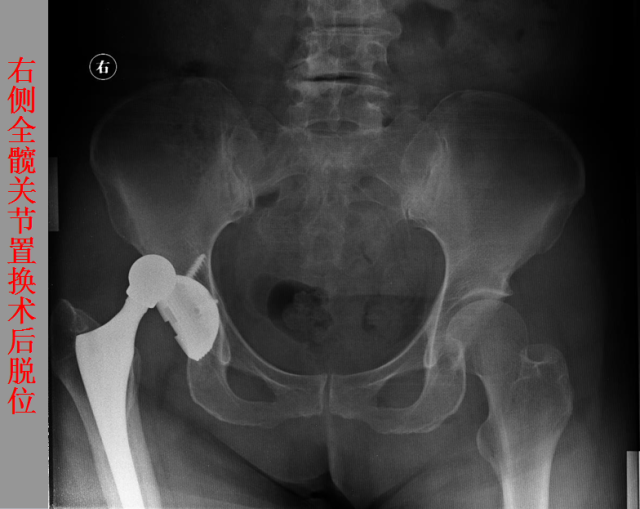

关节脱位篇

02

定义:关节脱位是暴力、关节感染、附近软组织挛缩或先天骨发育障碍造成的关节对位关系部分或完全脱离,即为半脱位或脱位。临床上以创伤性脱位*常见。